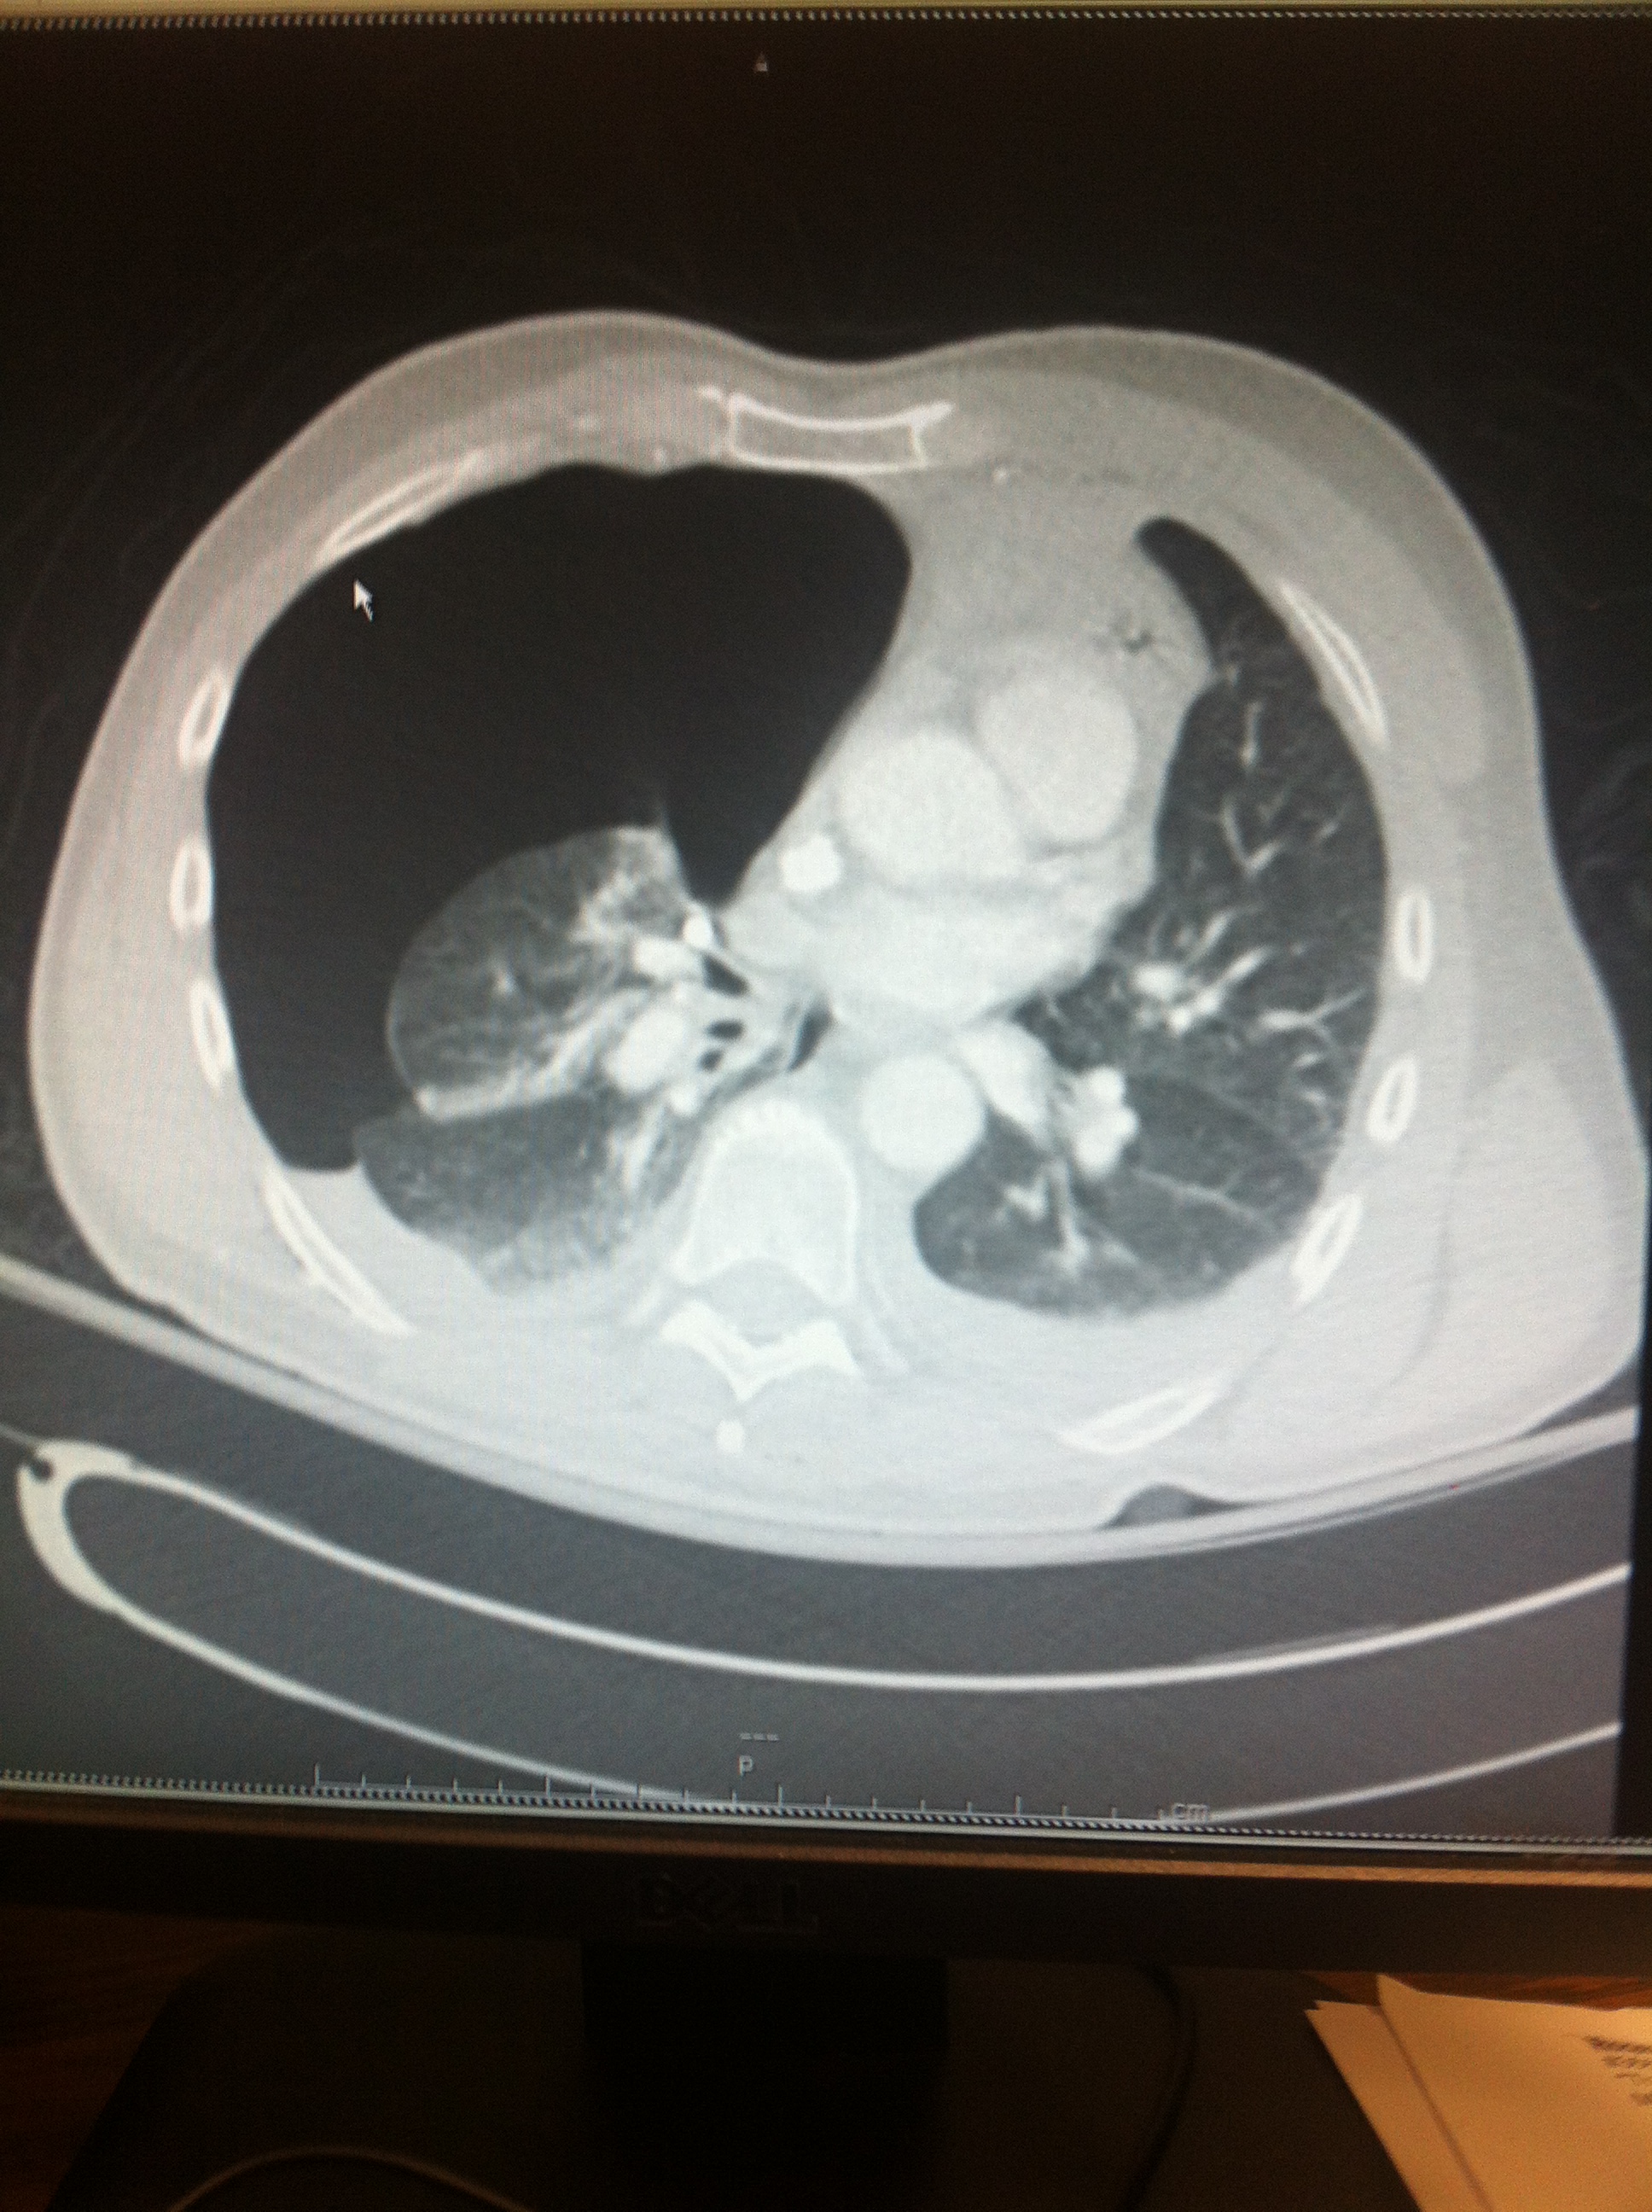

Patient is taken to CT at 23:05 (about 2 hrs after I ordered them) and the nurse grabs me after the scan and tells me I need to look at his chest CT (only his C-spine images were up at the time which showed me all kinds of SubQ emphysema).

His injuries included Bilateral 1st-6th Rib Fx’s, Pulmonary Contusions, Mediastinal Hematoma, Manubrium Fx, C7 Fx, T4, T7 Fx.